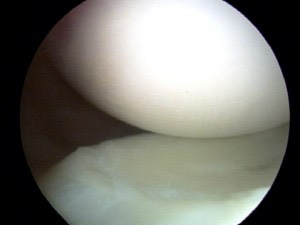

Smooth Knee Cartilage

Smooth Cartilage seen in the normal non-arthritis knee joint.

The knee is a critical joint.  Unfortunately it is also commonly injured and develops arthritis in many people.

The normal knee consist of smooth articular cartilage which is strong and resilient.  It allows the knee to move smoothly and without pain.